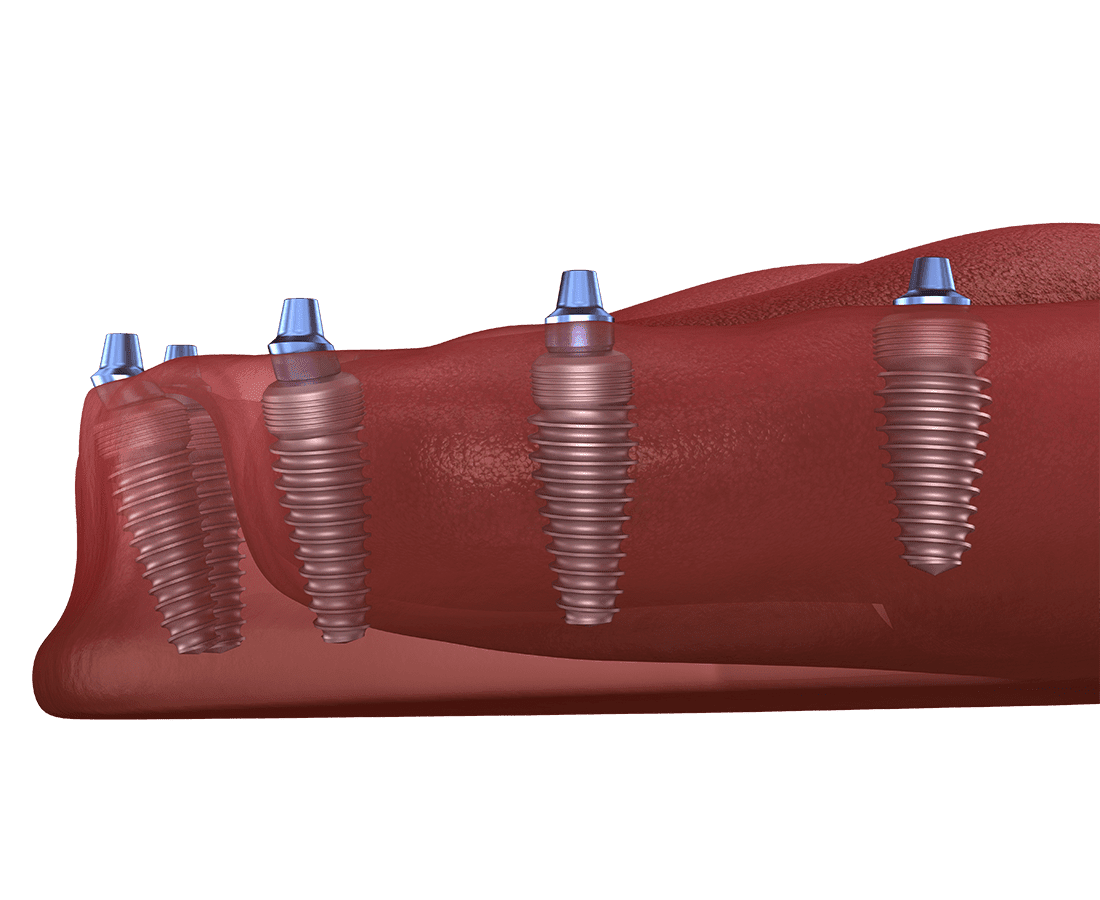

With All-on-4 implants, we don't replace the lost individual teeth.

Your dentist inserts four titanium posts into your jawbone to act as anchors. They then attach a permanent prosthetic that looks and functions like your natural teeth.

Your dentist begins the process by inserting the titanium screws into your jawbone. They place two front and two back implants in your mouth to distribute the force from the prosthetic. After placing the implants, they clean the surgical sites and suture all the incisions.